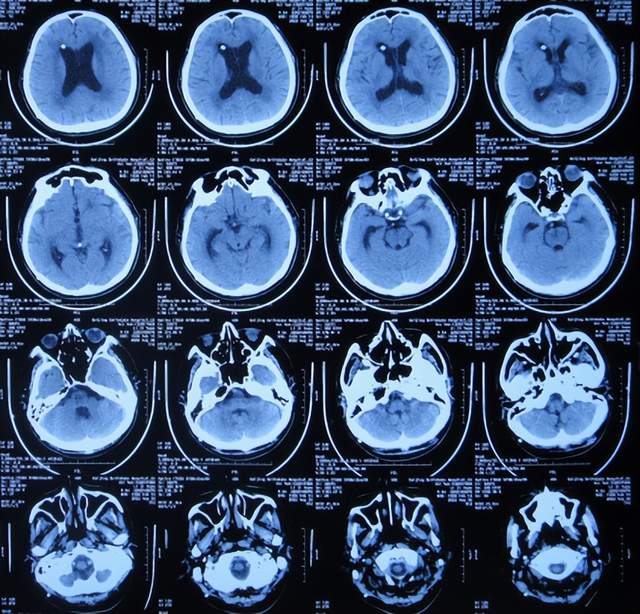

入院时查头颅CT示脑积水(图-13);肺部CT示肺部感染(图-14)。

图-13:2022年2月16日头颅CT

入院次日,给予脑室外引流术,查头颅CT示脑室外引流术后状态(图-15)。

图-15:2022年2月17日头颅CT

2022年3月1日(入院治疗13天),病情进一步改为:意识便完全正常,大小便变正常,扶着能坐起,言语交流变基本正常(图-17);头颅CT示脑室变小(图-18)。

图-18:2022年3月2日头颅CT

2022年4月7日(入院治疗50天),查头颅CT示脑室引流术后状态,未见异常(图-22)。

图-22:2022年4月7日头颅CT

2022年4月27日(入院治疗70天)家属要求出院回家休养。出院时:携带脑室腹壁外引流管;精神变得挺好,能自己站立但自己走路不稳,体重较入院时明显增加,入院时消瘦病态的体型已基本恢复正常状态(图-23);出院时头颅CT示脑室引流状态(图-24)。

图-24:出院时头颅CT